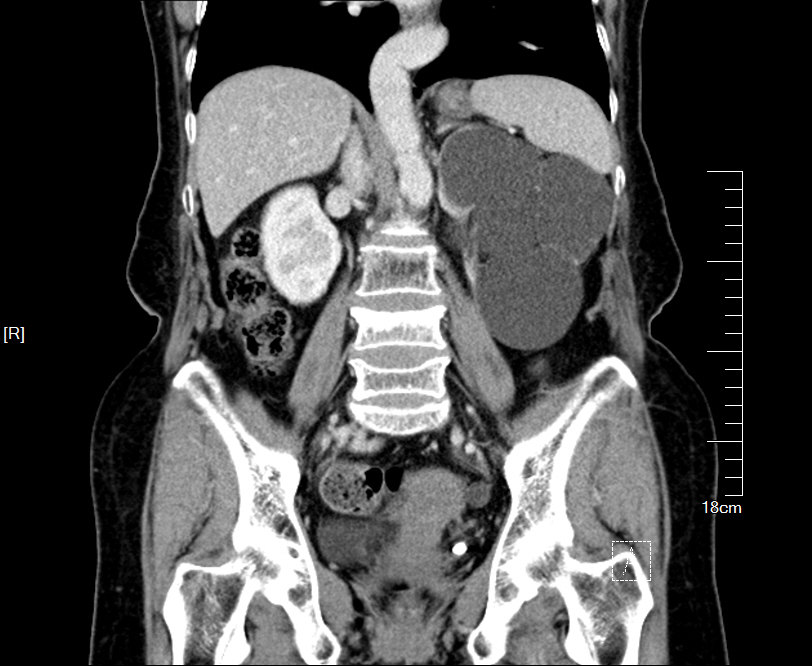

2016年04月手术患者,男性,37岁,盐城人,十七年前曾因左输尿管结石引起肾绞痛在当地予以多次震波碎石,疼痛缓解后未于重视,其间未予复查,一直于当地务农,自称今年来苏打工,招工体检时发现左肾重度积水一周来院求诊;CT:左侧肾脏重度积水,皮质菲薄,左侧输尿管结石约1.5cm,GFR:左侧4.89ml/min,右侧56.9ml/min。因右侧健肾代偿,肾功能正常:Cr 98umol/L;术前诊断:左输尿管结石 左肾重度积水 左肾无功能,鉴于左输尿管结石梗阻时间太长,左肾已几乎无功能,呈现皮囊肾样改变,最终只能行腹腔镜下左侧肾输尿管切除术,一并取出皮囊肾和输尿管及结石。

增强CT检查提示:左侧肾脏重度积水 皮质菲薄,几乎已无功能

左侧输尿管结石约1.5cm

GFR:左侧仅4.89ml/min,与增强CT检查相符